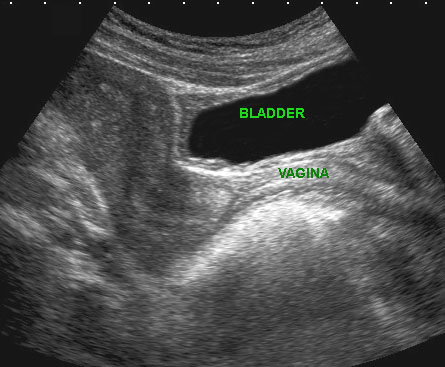

Các hình ảnh này của một phụ nữ trẻ bệnh nặng, đau nhiều với viêm phúc mạc toàn thể và CRP 250, nghi ngờ lâm sàng là thủng ruột thừa.

Siêu âm cho thấy ruột non mất nhu động (b.).

Không quan sát được ruột thừa.

TVUS cho thấy tử cung bình thường và buồng trứng bình thường (đầu mũi tên), được bao quanh bởi mô tăng âm (*).

CT xác nhận hình ảnh liệt ruột và ruột thừa bình thường (mũi tên).

PCR dương tính với lậu cầu.